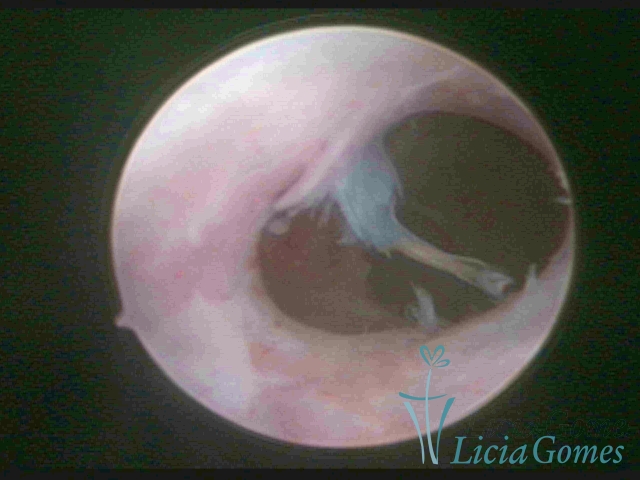

FIBROUS SYNECHIA

Uterine synechiae are scars (adherence) between the surface of the uterine walls, which may occur after the surgical procedure, uterine curettage, or after an inflammatory process in the uterine cavity (endometritis), which may lead to menstrual changes, infertility and obstetric complication such as abortion and premature birth.